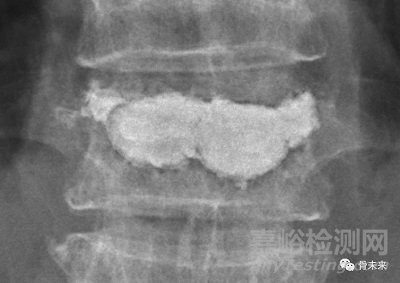

骨填充囊袋產(chǎn)品可適用于因骨質(zhì)疏松導(dǎo)致的椎體壓縮性骨折,在經(jīng)皮椎體成形術(shù)中對椎體的填充與穩(wěn)定。

凱利泰囊袋采用聚對苯二甲酸乙二醇酯(PET)材料制成,且使用獨特的網(wǎng)孔編織設(shè)計。在椎體成形手術(shù)中進行骨水泥注入時,囊袋既能包裹住骨水泥,避免其隨意流動及分布,又能允許骨水泥在達到囊袋額定容量后撐開囊袋,透過囊袋的網(wǎng)孔向外滲出形成突起。這樣既滿足了骨水泥的包裹需求,又允許其分散滲出,形成錨定鉸鎖,使傷椎保持一定的強度和剛度,提高脊柱穩(wěn)定性。